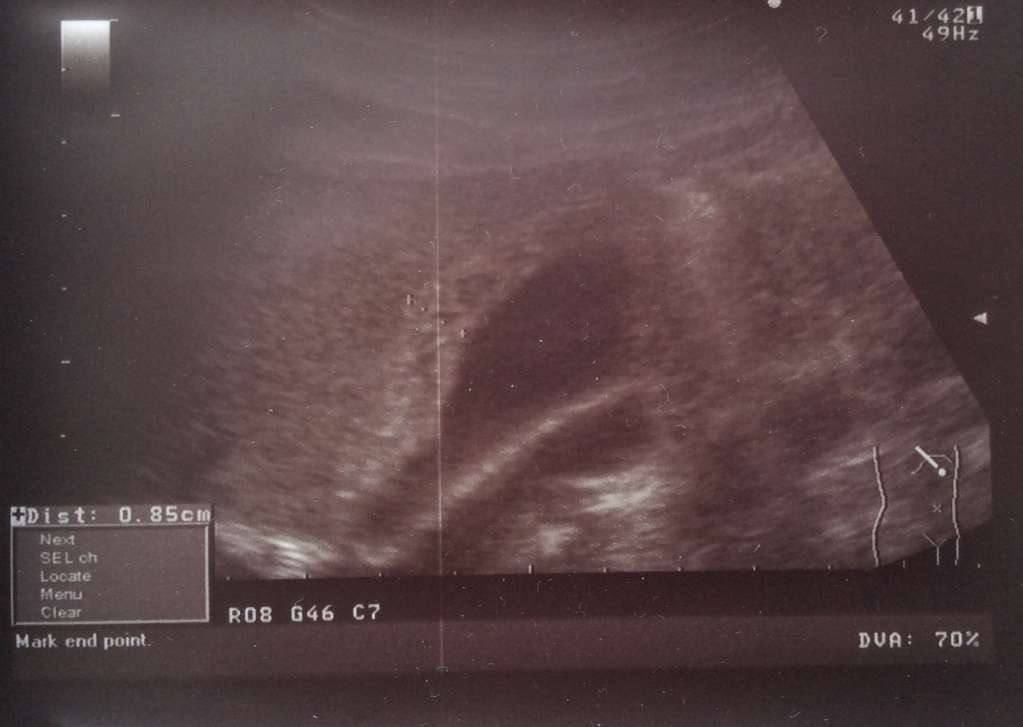

УЗИ ЖКБ Острый калькулезный флегмонозный холецистит фото